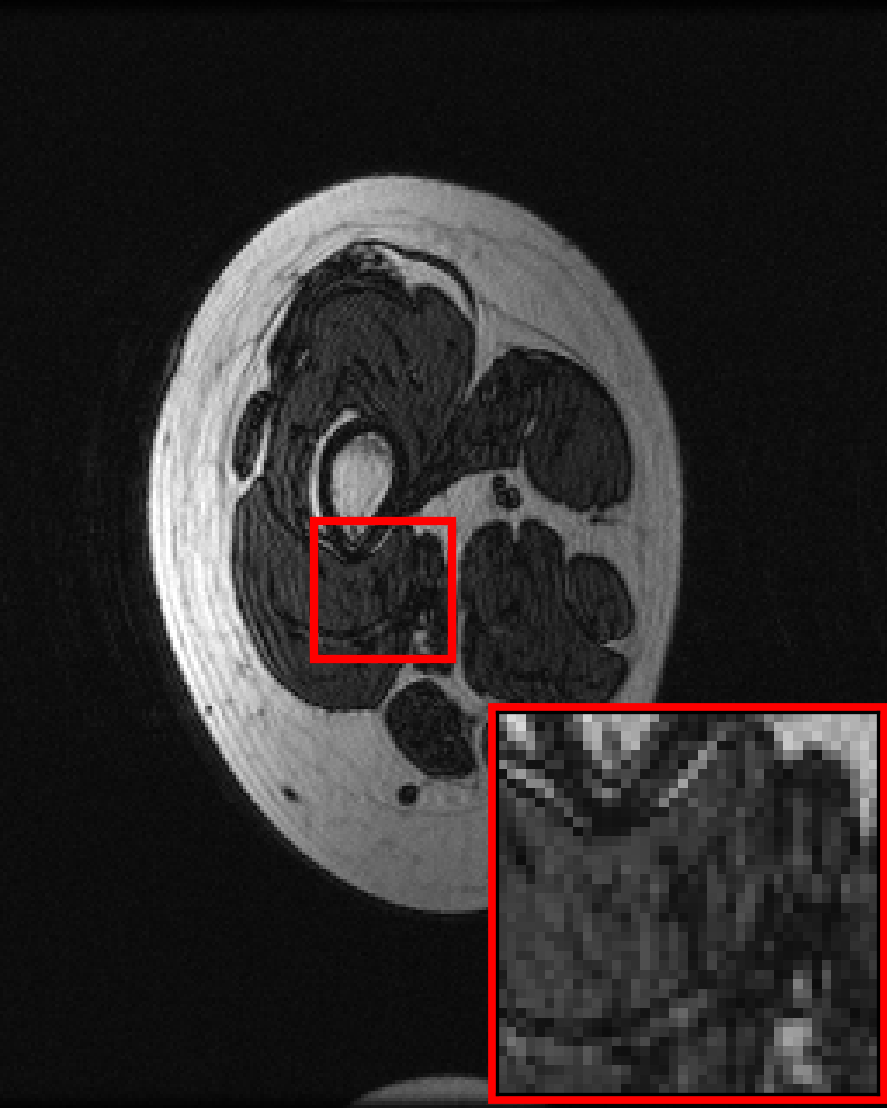

Many of our experiments are based on splits of the fastMRI dataset \citepzbontarFastMRIOpenDataset2019a, the most commonly used dataset for MRI reconstruction research. Figure 2 depicts samples from the fastMRI dataset and shows that MRI data vary in appearance across different anatomies and image contrasts (T1, T2, etc.). The image distribution also varies across vendors and magnetic field strengths of scanners, as the strength of the magnet impacts the signal-to-noise ratio (SNR), with stronger magnets leading to higher SNRs.

The fastMRI dataset stands out for its diversity and size, making it particularly well-suited for exploring how different data distributions can affect the performance of deep learning models for accelerated MRI. In our experiments in Section 3, 4, 5, and 6 we split the fastMRI dataset according to different attributes of the data. In Section 7, we showcase the generalizability of our findings on a diverse collection of 17 different datasets.

We consider two distributions and , and train U-nets \citepronnebergerUNetConvolutionalNetworks2015a, ViTs \citepdosovitskiyImageWorth16x162021b and end-to-end VarNets \citepsriramEndtoEndVariationalNetworks2020b on data from distributions and on data from distribution separately. We also train the same models on data from and , i.e., . We then evaluate on separate test sets from distribution and . We consider the end-to-end VarNet because it is a state-of-the-art model for accelerated MRI, and consider the U-net and ViT as popular baseline models. This diverse selection of architectures (unrolled, convolutional, transformer) aims to demonstrate that our qualitative results are independent of the specific architectural choice. We consider the following choices for and , which are subsets of the fastMRI dataset specified in Figure 2:

Contrasts. We select as PD-weighted knee images from 3 different scanners and are PDFS-weighted knee images from the same 3 scanners.

We are given data from two distributions and , where distribution can be split up into sub-distributions . We consider the following choices for the two distributions, all based on the knee and brain fastMRI datasets illustrated in Figure 2: